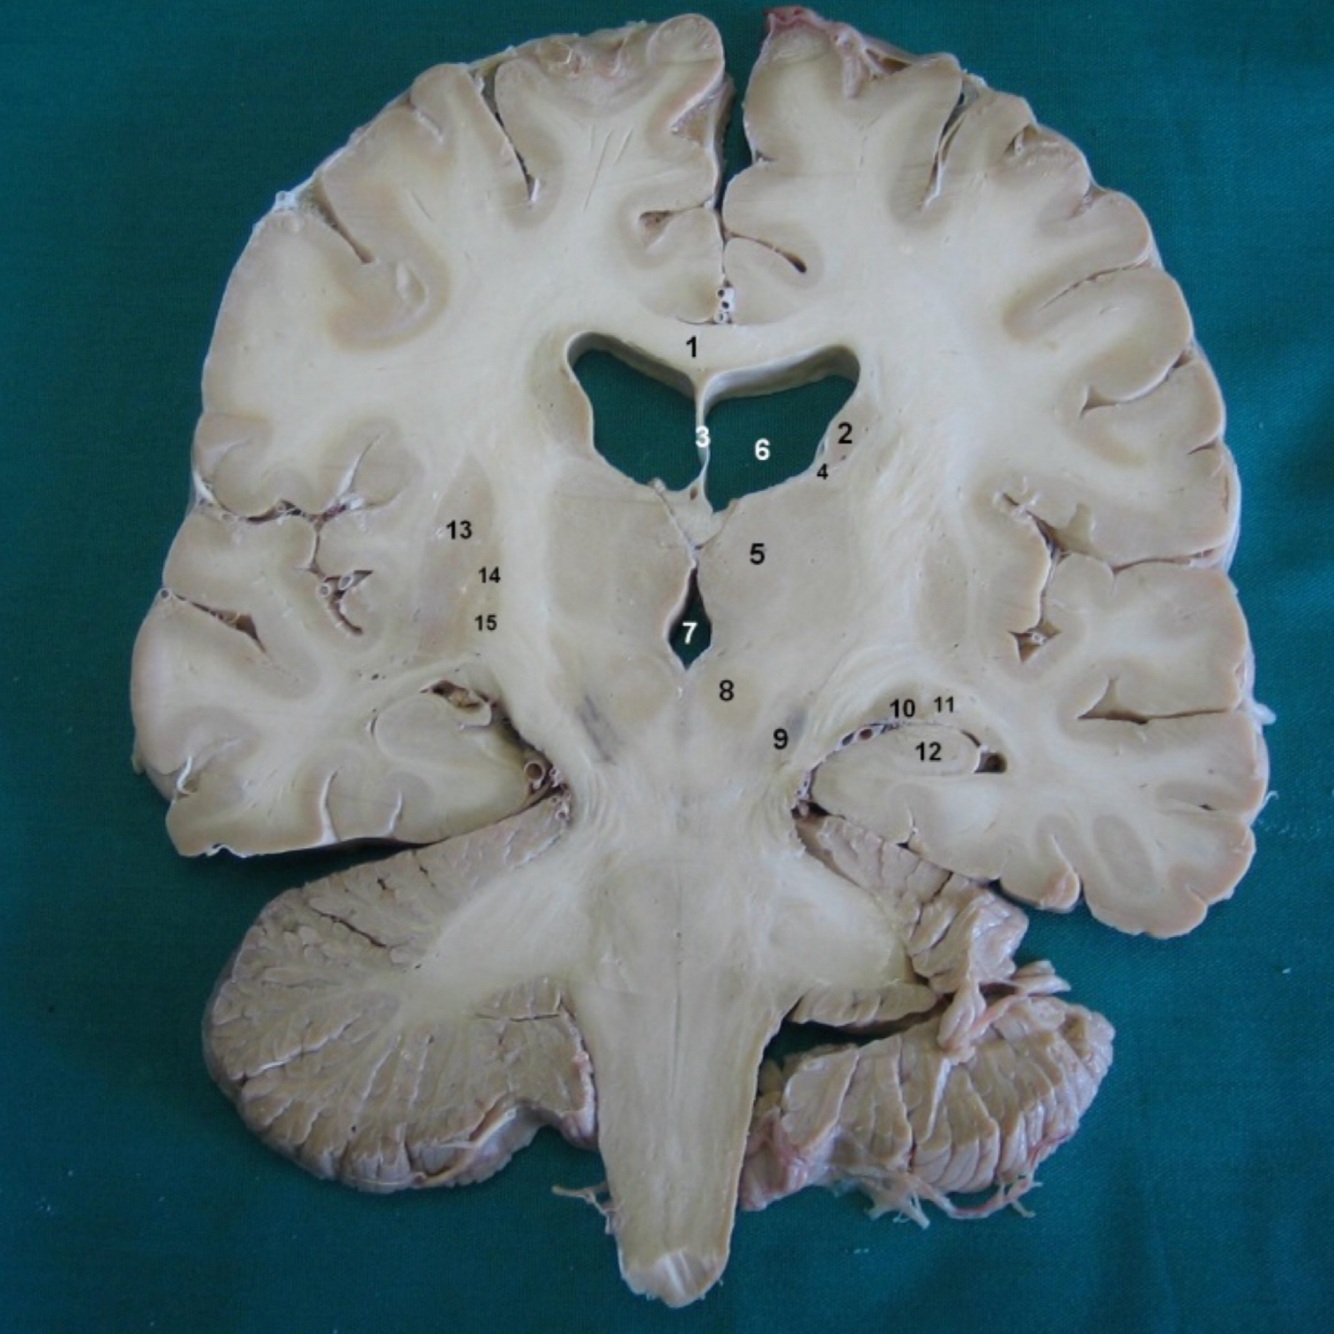

Contents of central nervous system

Brain and spinal cord

What is grey matter?

Mostly cells bodies, also glia and vessels

What is white matter?

Mainly axons (in nerve fibers) and oligodendrocytes (mielin), also glia and vessels

What do ventricles contain? How many do we have?

Cerebrospinal fluid. We have 4.

In brain, the gray matter is in the…

Cerebral cortex

All the information that has to go to the cortex, passes before by the…

Thalamus

Parts of the cerebrum

Cortex (cerebral hemispheres) and diencephalon (thalamus)

Within the cortex: frontal, parietal, temporal and occipital lobes divided by fissures (sulcus)